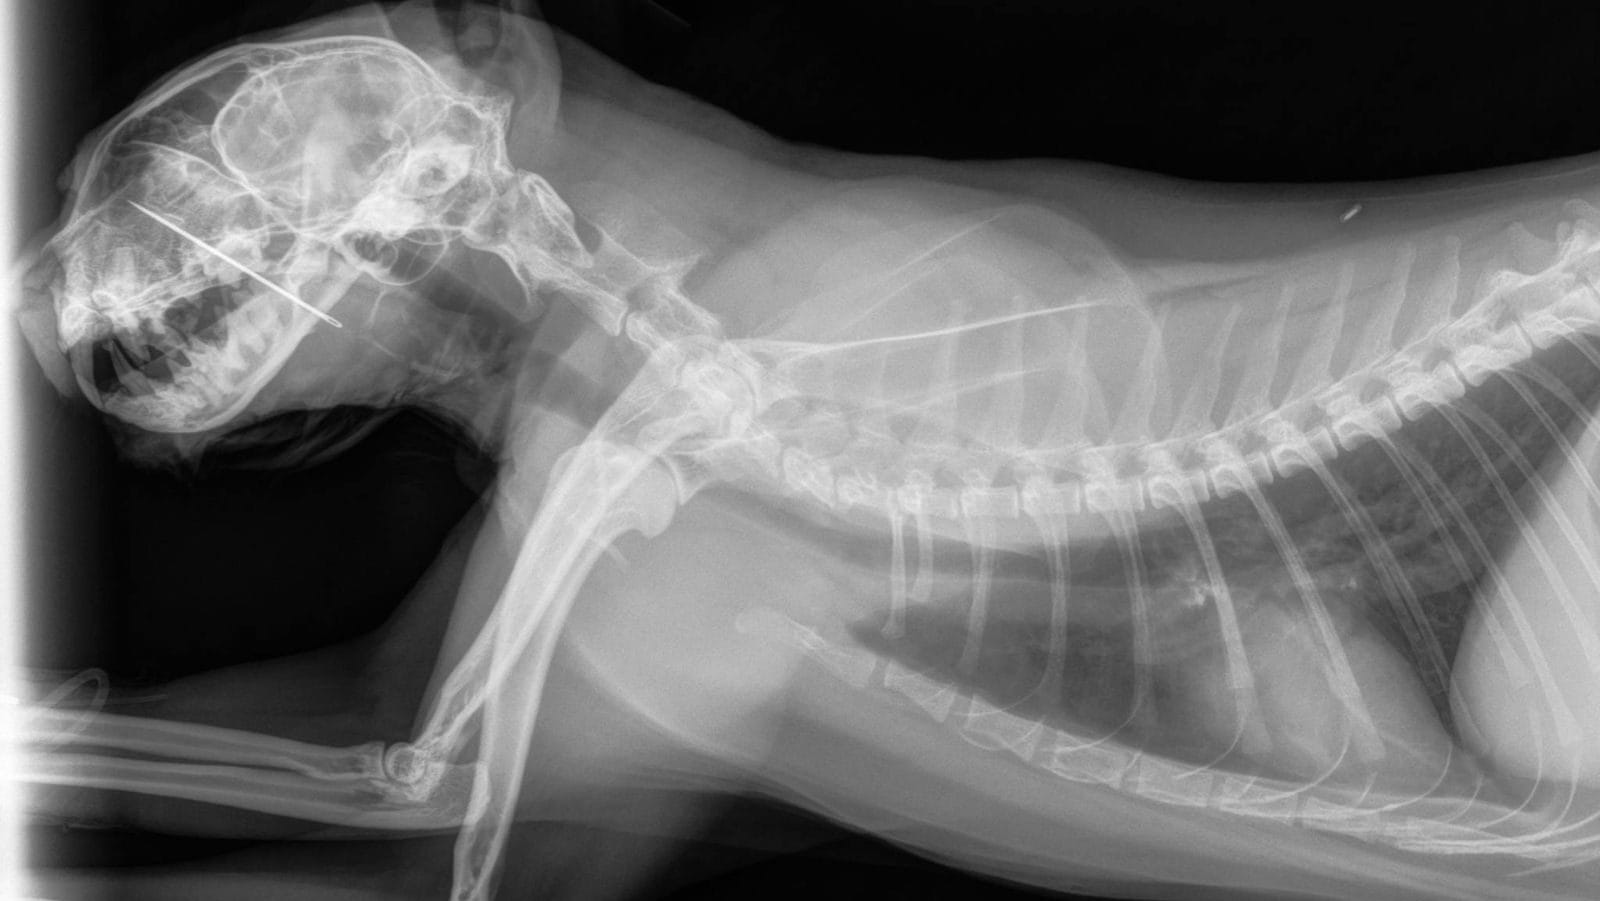

A sewing needle, almost two inches long, was lodged deep in Kevin’s mouth.

It had pierced his hard palate and extended up into his nasal cavity, a spot that’s incredibly difficult to reach and can cause intense discomfort. It was no wonder Kevin was in such distress.

The medical team acted quickly. Using their specialized equipment and surgical skills, they managed to remove the needle completely.